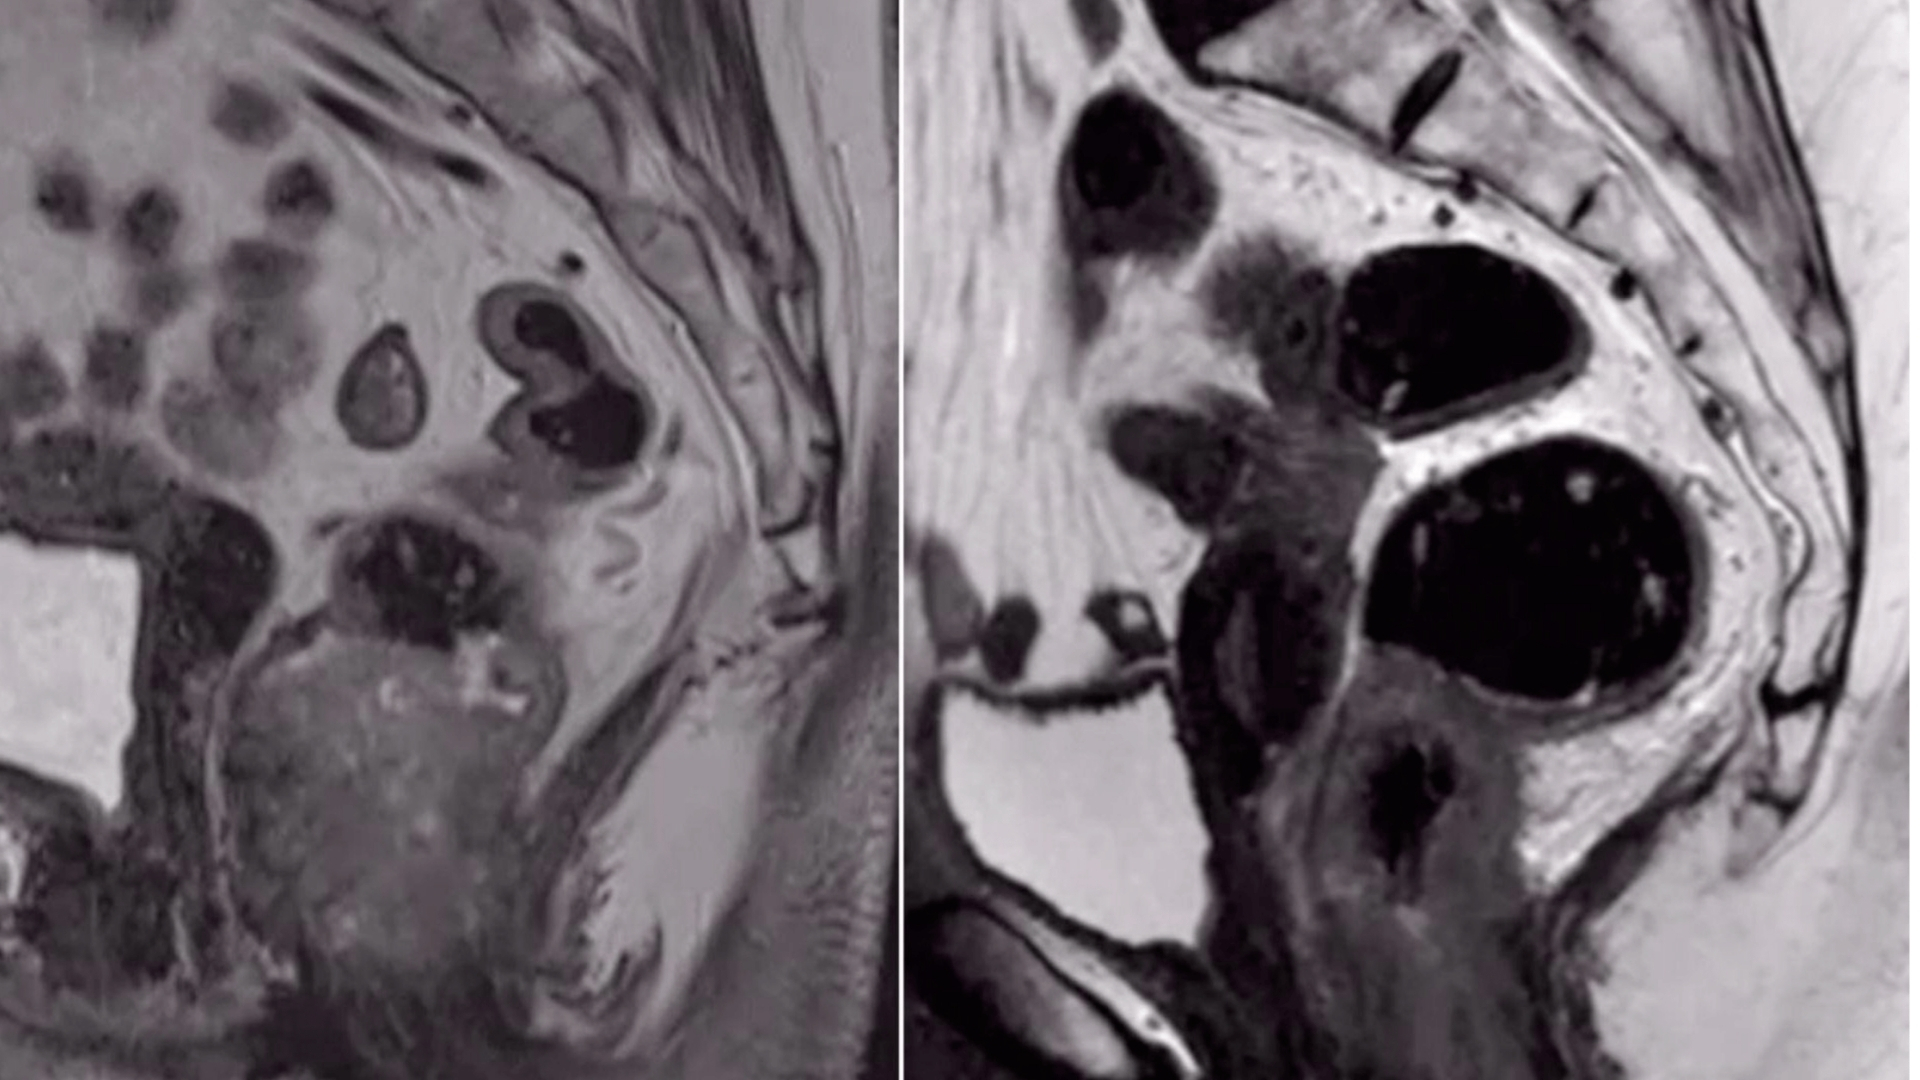

• Advanced Diagnostics: State-of-the-art imaging (e.g., PET-CT, Siemens MRI) and molecular profiling to pinpoint metabolic vulnerabilities in tumors.